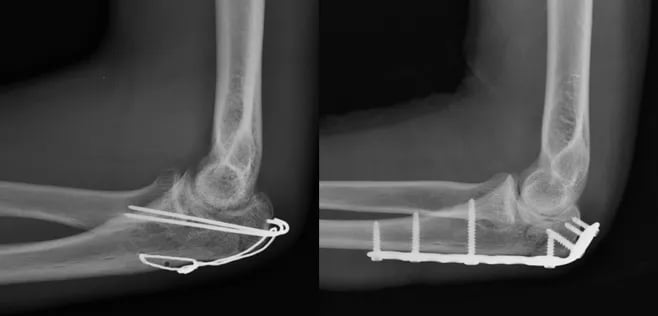

Fratura do Olécrano

O olécrano é uma parte da ulna, um dos ossos do antebraço. Ele se articula com o úmero no cotovelo. As fraturas desse local costumam ocorrer após queda sobre a mão ou traumas diretos sobre o cotovelo.